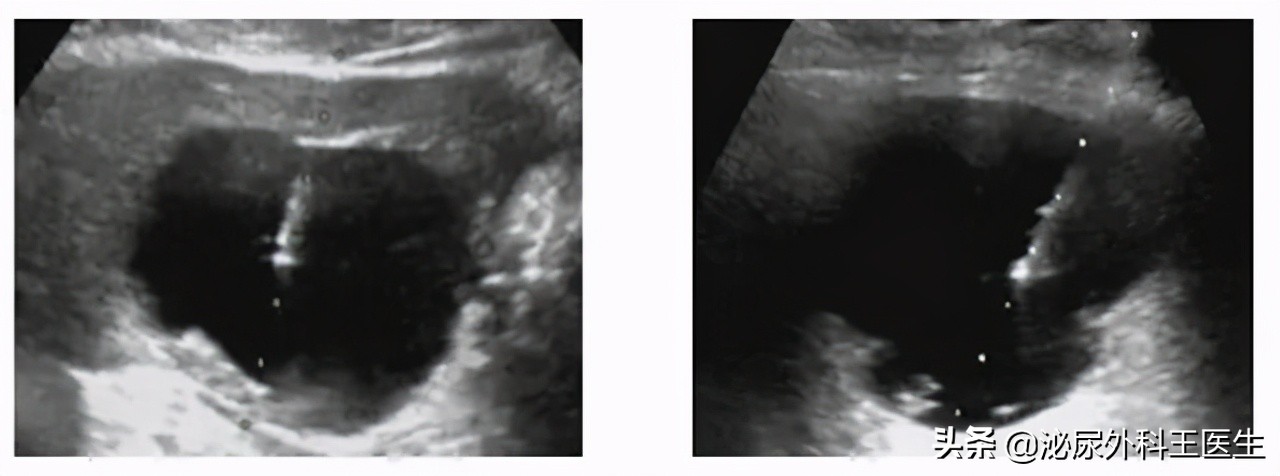

B超是目前为止,对于诊断肾囊肿的最准确的检查方式。 B超就能分出以上三种的肾囊肿的情况,遇见比较难的情况,也可以通过CT、MAI等也可以诊断。再配合尿检与肾功能检查,可以得知如何治疗。

其实,肾脏囊性病变的具体分型需要依靠影像检查分辨。

影像表现:水样密度,没有强化,也就是说里面物质清亮,具有发线样囊壁,没有钙化、实性成分。